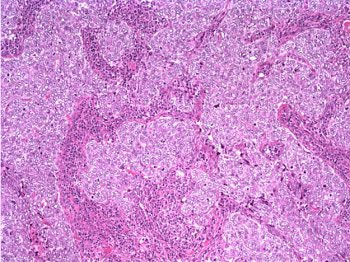

The patient underwent a lumpectomy with sentinel node biopsy. The pathology again showed extensive mitoses consistent with grade III invasive ductal carcinoma. Figure 4 (below) shows a representative microscopic section of the mass 4 cm from the nipple at a magnification factor of 100x. Figure 5 is the same area magnified 400x. Figure 6 shows a representative microscopic section from the other mass, which was 3 cm from the nipple magnified 100x. Figure 7 is magnified 400x. The tumors were estrogen receptor- and progesterone receptor-negative. Two sentinel nodes were negative.

![]() |

|

Figure 6: Above, IDC right breast, 10 o'clock, 3 cm from the nipple magnified 100x. Figure 7: Below, IDC right breast, 10 o'clock, 3 cm from the nipple magnified 400x. |